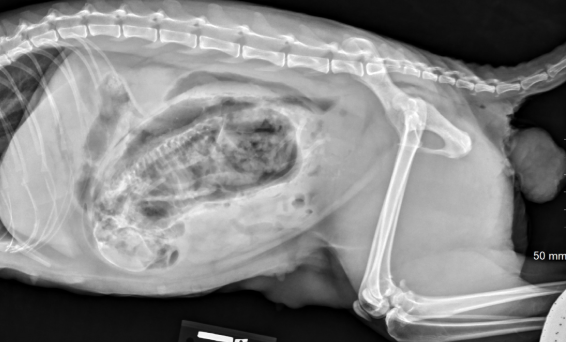

What fetal position is observed that would result in dystocia?

Breech